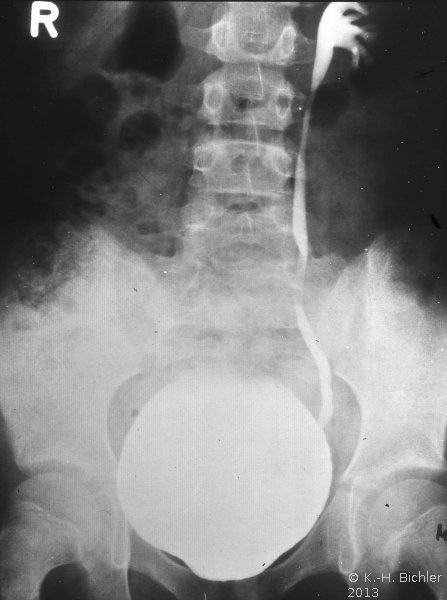

Neben der Anamnese, körperlicher Untersuchung, Messung des Blutdruckes sowie der Laboruntersuchungen: Urinstatus, Serumkreatinin und -Elektroylte ist die Sonographie zur Feststellung einer einseitig kleinen Niere zielführend (Abbildung 10a). Zur Diagnostik zählt fernerhin die NFZG (Abbildung 10b) bzw. Computertomographie.

Computertomographie zur Diagnostik der kleinen Niere. Zum Beispiel eine pyelonephritisch veränderte linke Niere im Computertomogramm und im weiteren Beispiel CT und Organpräparat einer rechtsseitigen kleinen Niere.

Und in einem weiteren Beispiel CT und Organpräparat einer rechtseitigen "kleinen Niere" (Abbildung 11, 12ab).

Die Abbildungen zeigen die Anwendung von Sonographie und Miktionszysturethrogramm bei einer kleinen stummen Niere (Abbildung 13, 14).